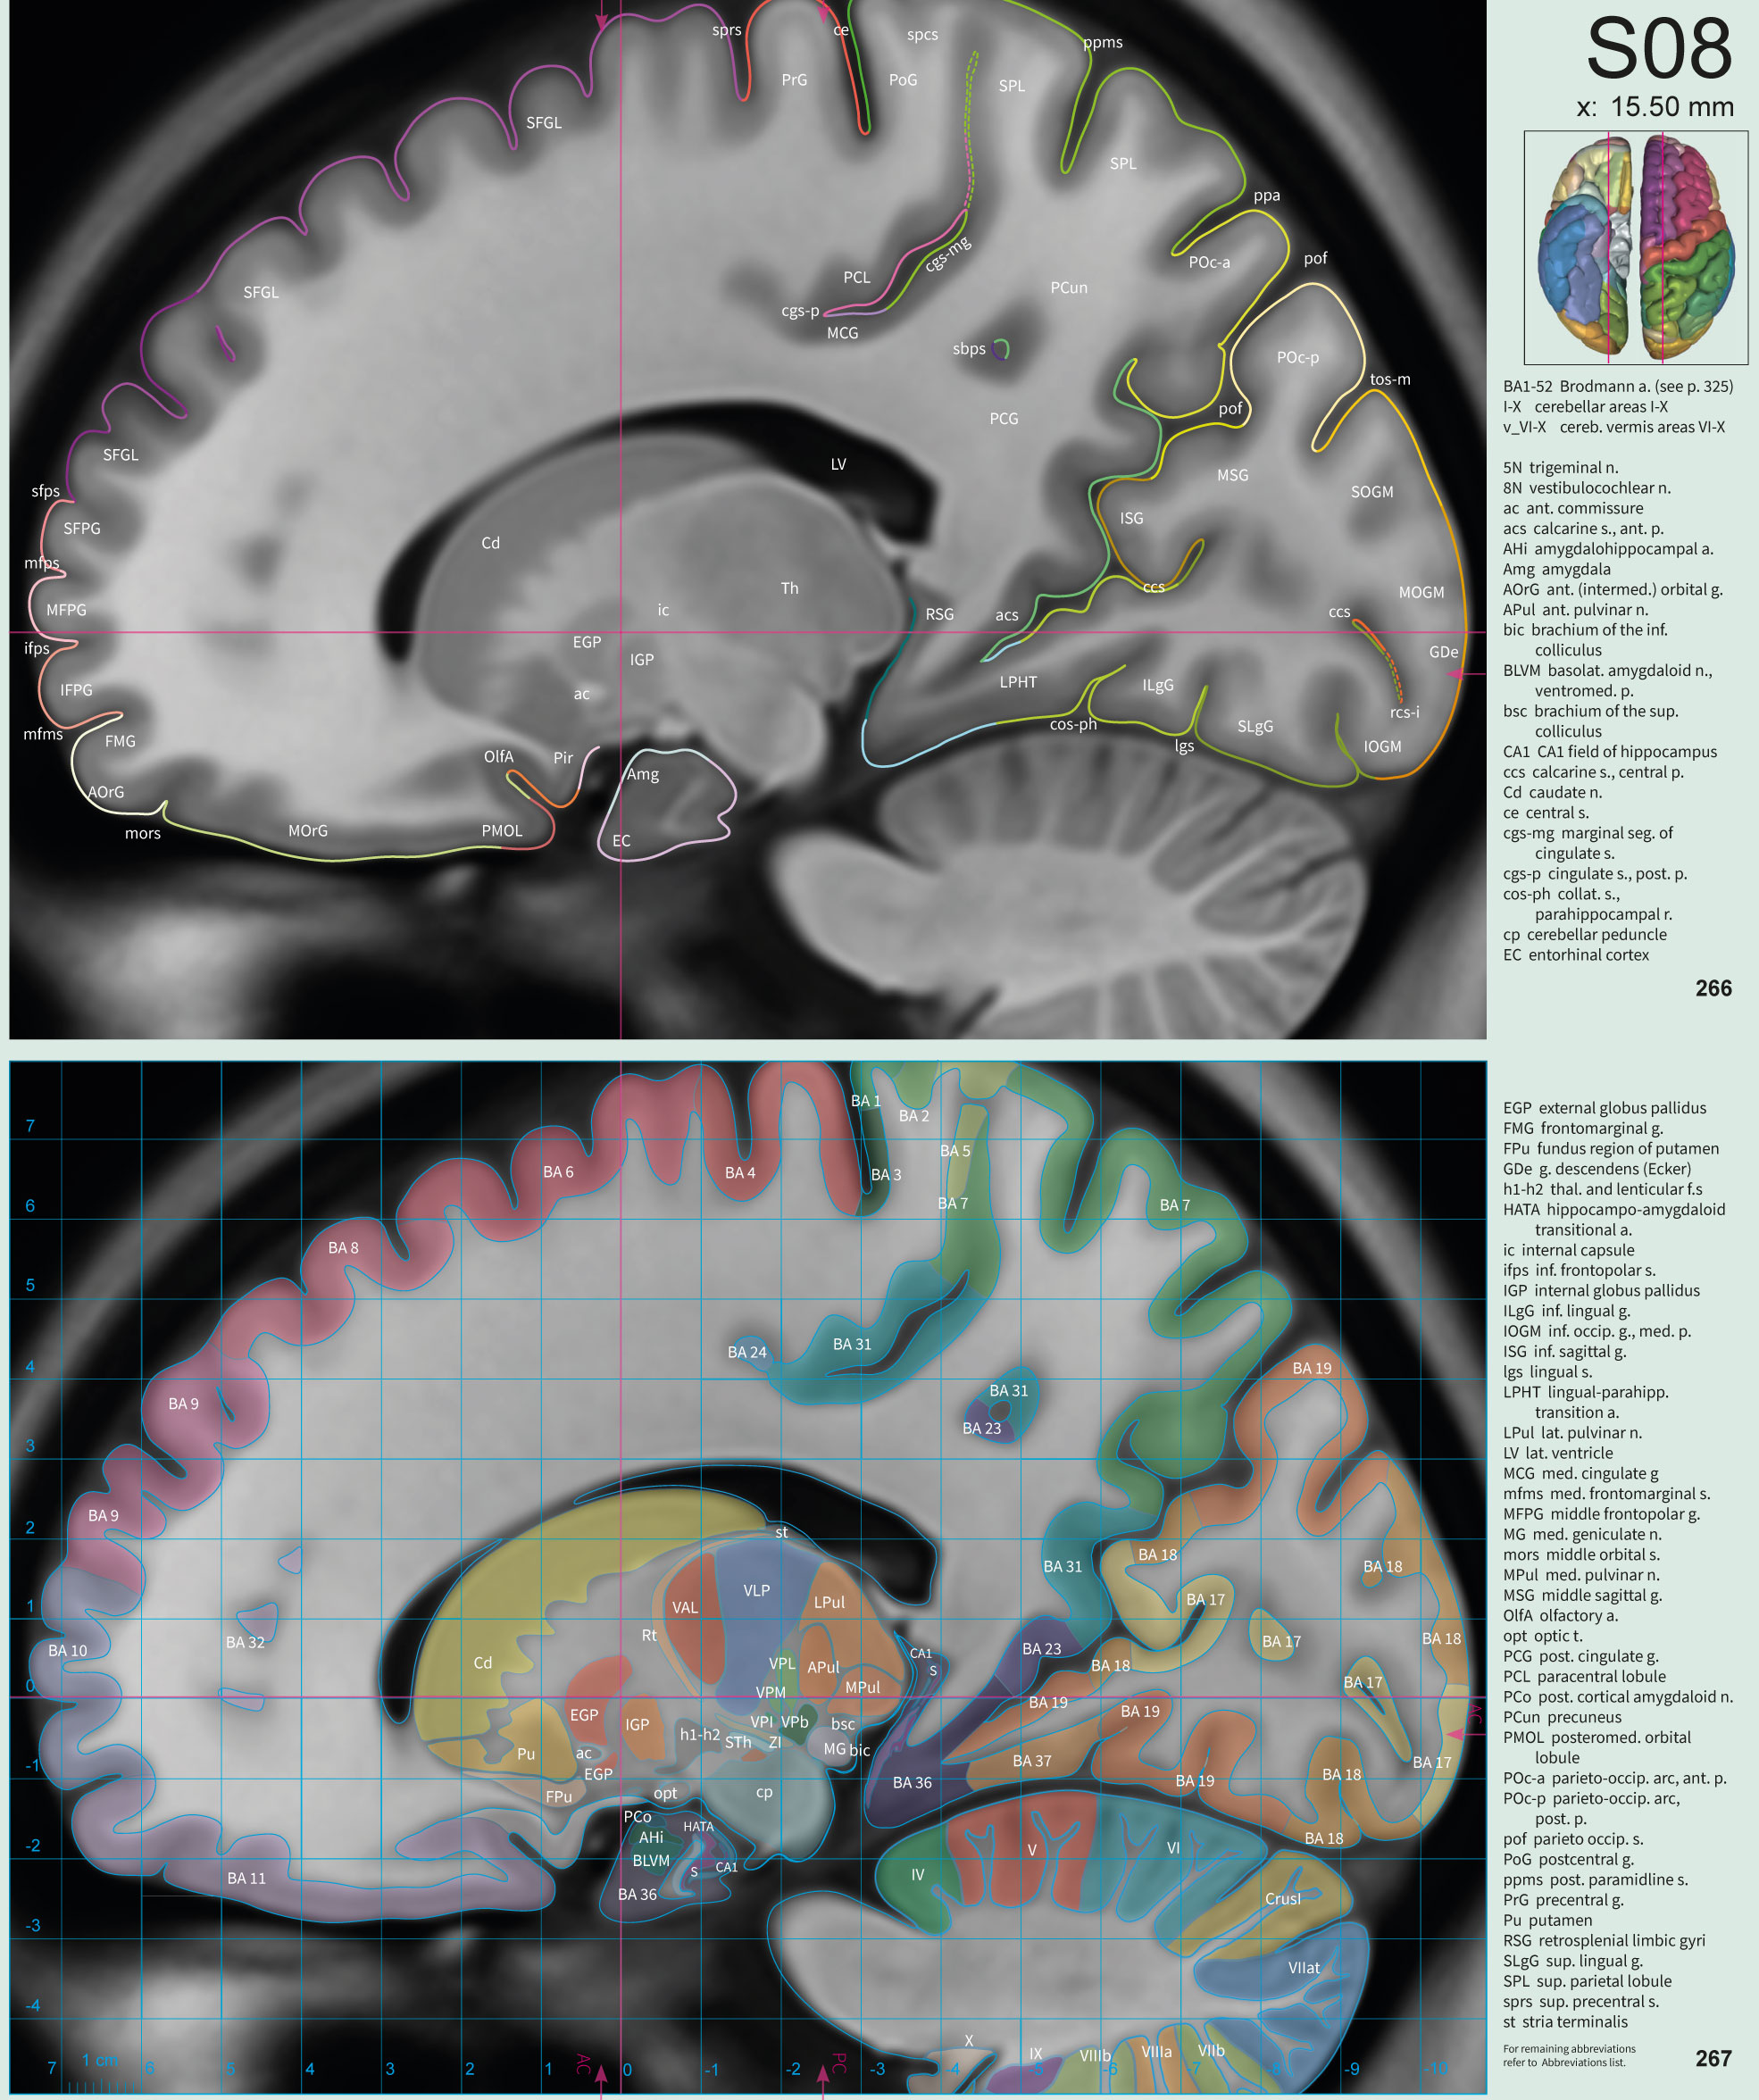

Sample pages

for the coronal, axial and sagittal sections

• Detailed sulco-gyral Cortex Designations

• Brodmann Areas delineated

Each drawing in the atlas shows the delineation of individual anatomical structures representing their cross-sectional area of the corresponding 3D model.